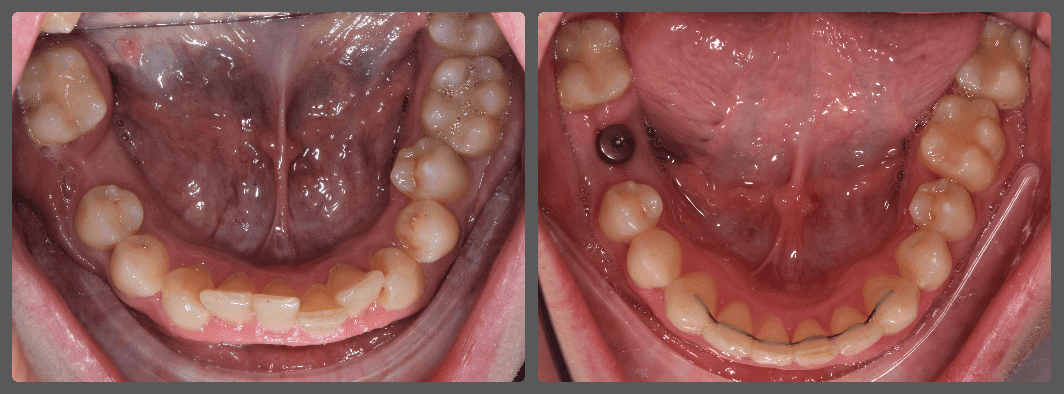

Balázs súlyos alsó torlódása miatt keresett fel magánrendelésemen. A diagnosztikus vizsgálatok során előbbin túl alsó-felső fogívszűkületet, valamint nyitott harapási hajlamot állapítottam meg. Kezelését Pitts21 alsó-felső rögzített fogszabályozó készülékkel kezdtük meg. A nyitott harapási hajlamot a hátsó fogakra helyezett harapásemelővel kontrolláltuk. A torlódott fogaknak tolórugóval és interproximális redukcióval teremtettünk helyet, és intermaxilláris gumihúzással tökéletesítettük a harapást. A fogszabályzó kezelés teljes időtartama alatt Balázs 110%-osan együttműködő volt, ezért 21 hónap alatt sikerült kiemelkedő végeredményt elérnünk.